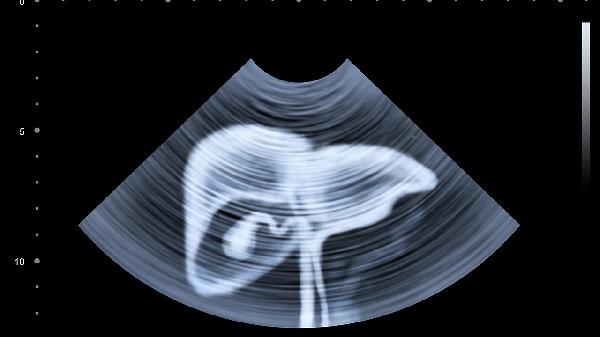

肾结石或输尿管结石也可能导致类似症状,因此如果疼痛持续或加重,建议尽快就医以获得专业诊断和治疗。保持健康的生活方式,注意饮食和水分摄入,可以有效预防这些问题的发生。无论是哪种情况,及时就医都是确保健康的关键步骤。